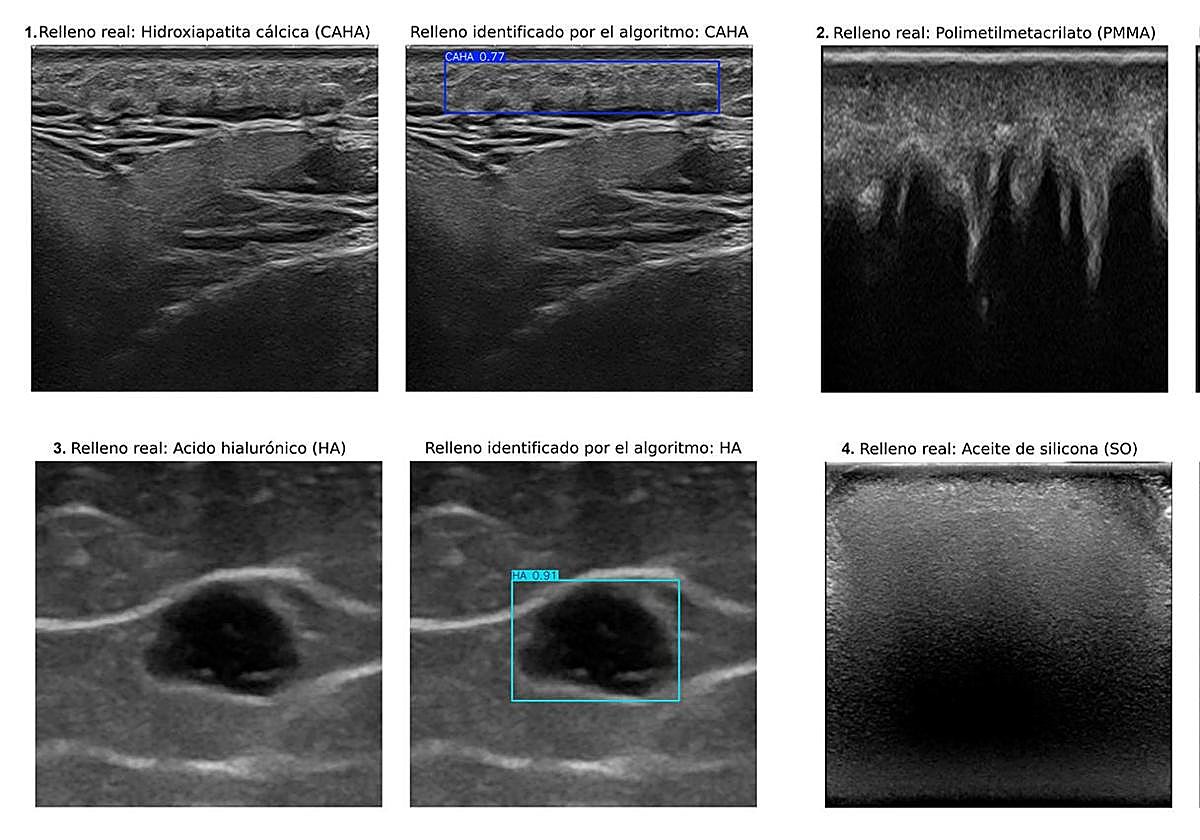

El equipo de investigación dirigido por la doctora Ximena Worstman de la Universidad de Chile, que ha contado con la decisiva participación de los profesores del Departamento de Ciencias de la Computación e Inteligencia Artificial de la Universidad de Granada Manuel Lozano y Francisco J. Rodríguez, ha creado un sistema de inteligencia artificial basado en aprendizaje profundo. Este algoritmo es capaz de identificar y discriminar automáticamente, en imágenes ecográficas, cuatro tipos de rellenos cosméticos: hidroxiapatita cálcica, ácido hialurónico, polimetilmetacrilato y aceite de silicona.

El estudio se ha desarrollado en un contexto multicentro internacional, con la participación de especialistas en dermatología. Para entrenar al sistema, se utilizaron equipos ecográficos de diversa complejidad, desde unidades portátiles de pequeño tamaño hasta dispositivos de alta gama, garantizando así la adaptabilidad del sistema a diferentes entornos clínicos.